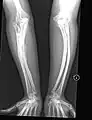

OI Type V in a child

Having the same clinical features as Type IV, it is distinguished histologically by "mesh-like" bone appearance. Further characterized by the "V triad" consisting of (a) radio-opaque band adjacent to growth plates, (b) hypertrophic calluses at fracture sites, and (c) calcification of the radio-ulnar interosseous membrane.[24]

OI Type V leads to calcification of the membrane between the two forearm bones, making it difficult to turn the wrist. Another symptom is abnormally large amounts of repair tissue (hyperplasic callus) at the site of fractures. Other features of this condition include radial head dislocation, long bone bowing, and mixed hearing loss.